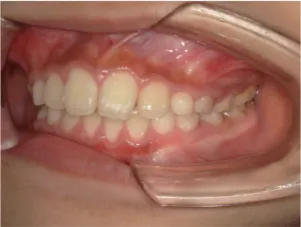

治療中③中1:拡大・前歯の並替え、トイシャー(出っ歯を治す装置)終了

*出っ歯、過蓋咬合、口唇閉鎖不全の改善

*咬合治療用モノブロック装置(筋機能的咬合誘導装置)へ移行

*口唇閉鎖不全がなおり奇麗な口元に改善